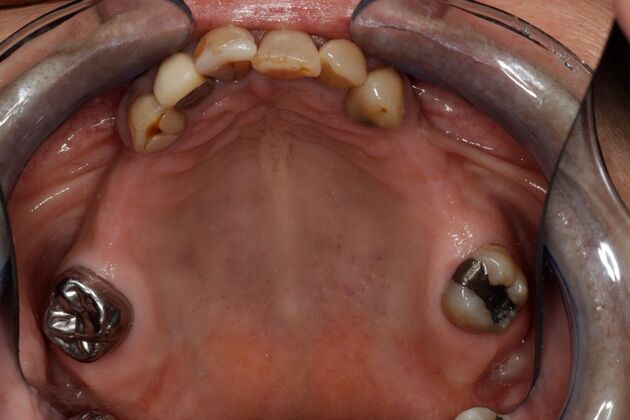

Removable partial dentures were left in a drawer for year and never worn because of their fit, food getting under them, and difficulty with speech. This patient finally got tired of not having back teeth to chew with and came to Dr Nordhus to discuss implant options. Due to her lack of bone structure a specialist placed the implants where her natural teeth were missing in the back. Dr Nordhus then restored her entire mouth to achieve her desires to be able to chew and have a beautiful smile.